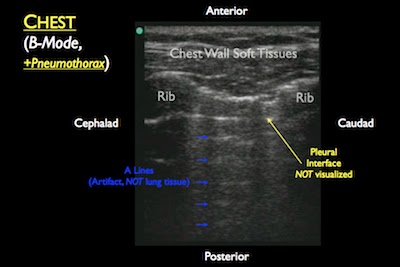

- Component: Pneumothorax

- Probe: Linear probe (7.5 – 10 MHz)

- Location: Midclavicular line, 3rd – 5th intercostal space

- Finding: Intrathoracic compromise

- Normal: Should see lung sliding and comet tails. M-Mode will look like “waves on a beach”.

- Pneumothorax present: NO lung sliding and NO comet tails. M-Mode will look like a “bar graph” (no beach).